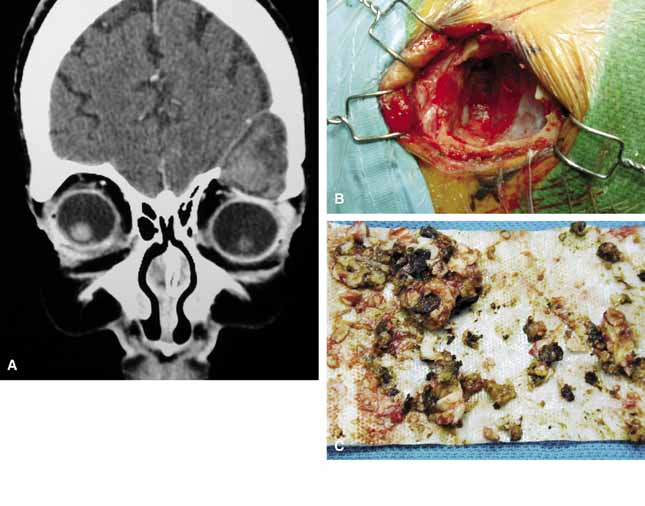

Because of the variable presentation of dermoid cysts, Shields et al.,5 have suggested a classification of orbital dermoid cysts by their association (or lack of association) with suture lines of the skull and assist the clinician in appropriate management. Cysts are classified as juxtasutural, sutural, or soft-tissue dermoid cysts. Those cysts adjacent to the bony suture line but not firmly attached are juxtasutural. A sutural dermoid cyst is firmly attached to bony sutures causing bone erosion, tunnels or an hourglass configuration. Soft tissue dermoid cysts may be strictly confined to soft tissues without any connection to a bone structure. Intradiploic epidermoid cysts are distinctly uncommon and were not included in Shields' classification (Fig. 3).

Fig. 3 In a coronal image of a computed tomogram, an intradiploic dermoid cyst is shown to involve the superior orbital rim and roof of the left orbit displacing the globe downward (A). The intraoperative cavity (B) of the cyst is observed with the evacuated keratin debris shown (C).